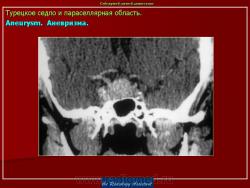

ГМ. Патология области турецкого седла. Набор изображений. +

Патология области турецкого седла.

впервые настолько глубокие изменеия турецкого седла, что даже не требуется дообследование.